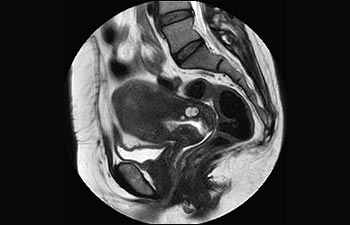

Encuentre la aplicación clínica adecuada a sus necesidades